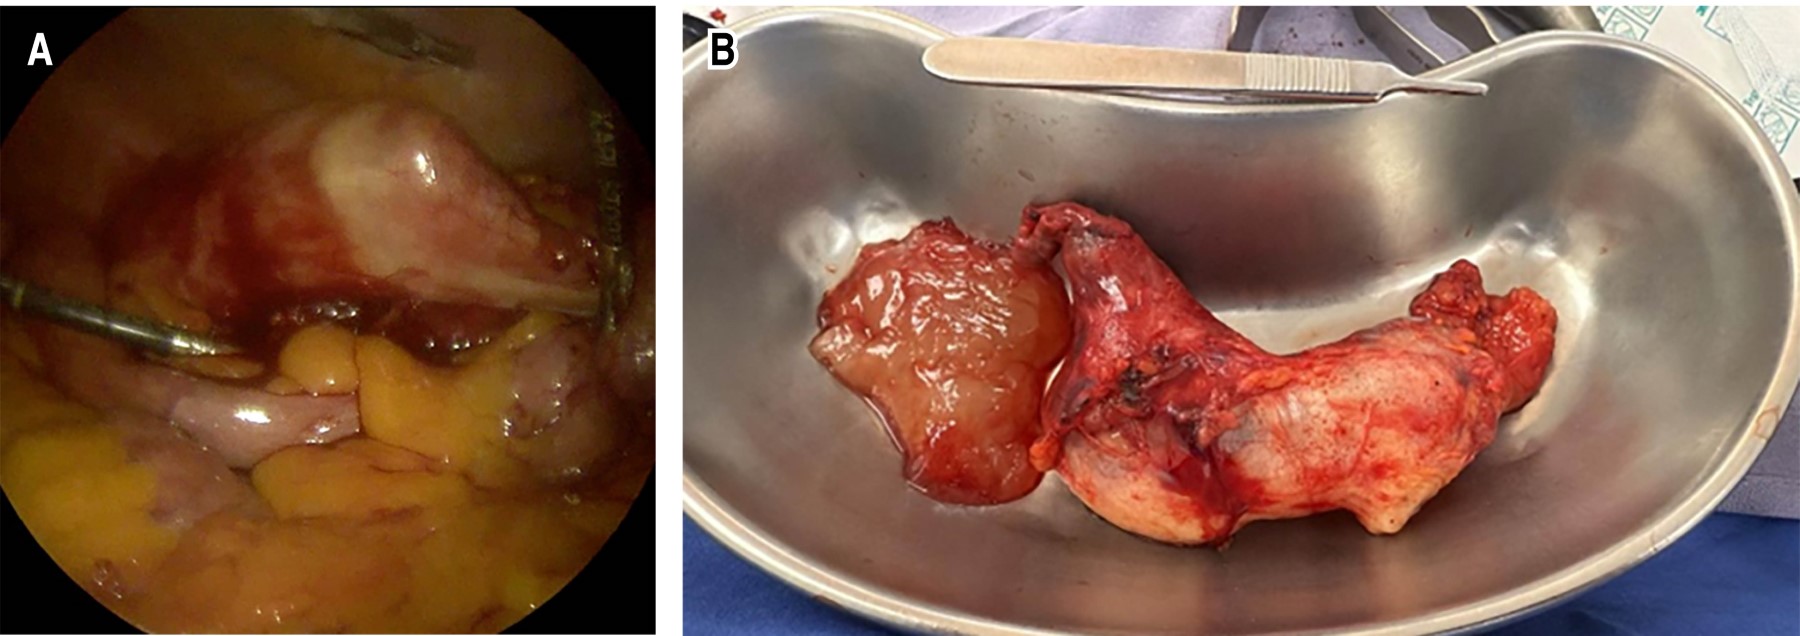

El tratamiento quirúrgico se inicia con una colecistectomía laparoscópica sin complicaciones. Durante la exploración de la cavidad abdominal, se evidencia un apéndice de aspecto patológico y gran tamaño, lo cual indica la necesidad de reconvertir a cirugía abierta para minimizar el riesgo de rotura. Se procede a realizar apendicectomía mediante incisión media infraumbilical (Figura 2). La evolución postoperatoria fue satisfactoria.

El estudio histopatológico definitivo reporta: neoplasia mucinosa apendicular de bajo grado, con márgenes quirúrgicos negativos para lesión neoplásica (Figura 3).

Figura 2

Figura 3